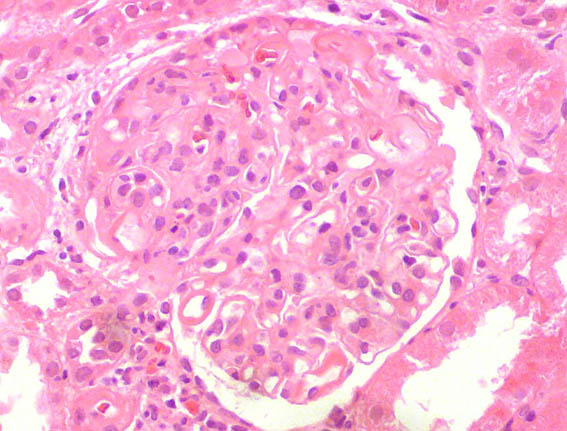

A renal biopsy was done, see the images.

Figure 2. H&E, X400.